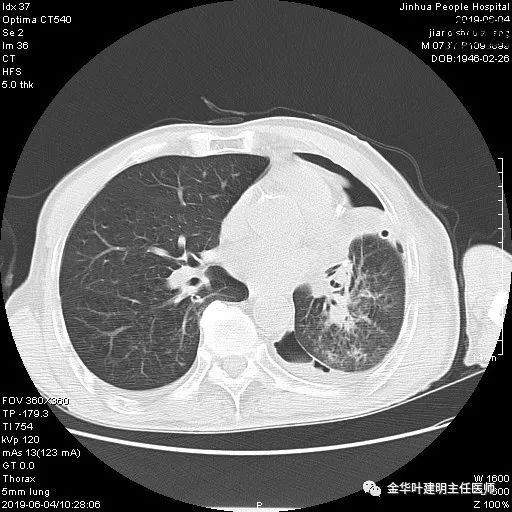

6.4上午:24小时引流出血性乳糜液1800毫升。是否再次手术进行右进胸胸导管结扎,抑或继续保守治疗非常纠结!压力非常大!!多方讨论会诊无法取得一致意见,但一般认为,引流量在1000毫升以上宜积极手术。情况与浙二医院范军强教授联系,请求指导,范教授认为左侧肺手术,损伤胸导管主干的机会较小,多数可保守治疗而愈。在他们的病例中,也有结扎胸导管后引流量仍无减少,效果并不能完全保证。建议可以考虑胸管夹管视察(因为淋巴管压力低,予以适当的压力,漏出量可能会明显减少),同时继续禁食,并静脉营养支持,引流管口可能会有渗液,关注更换敷料。与家属充分沟通后决定试夹管;这天血色素9.0 g/L;胸部CT复查示: